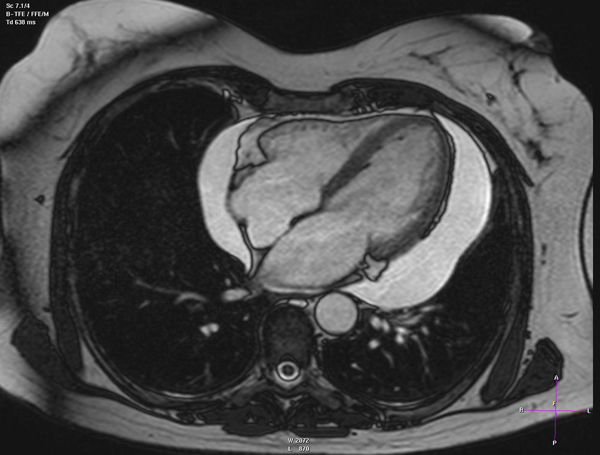

پریکاردیت

پریکاردیت و التهاب پرده های اطراف قلب